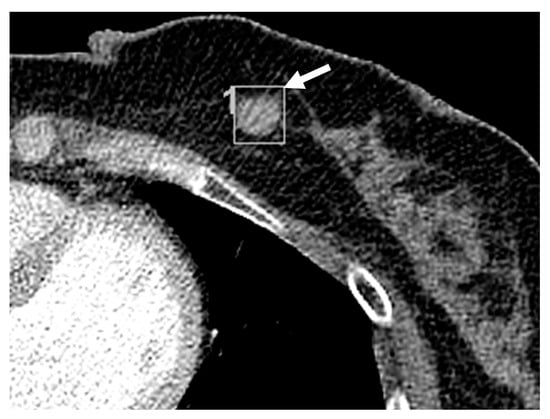

3.2. Imaging Features of Missed and Detected Breast Cancers

3.3. Imaging Features Associated with Missed Breast Lesions Group